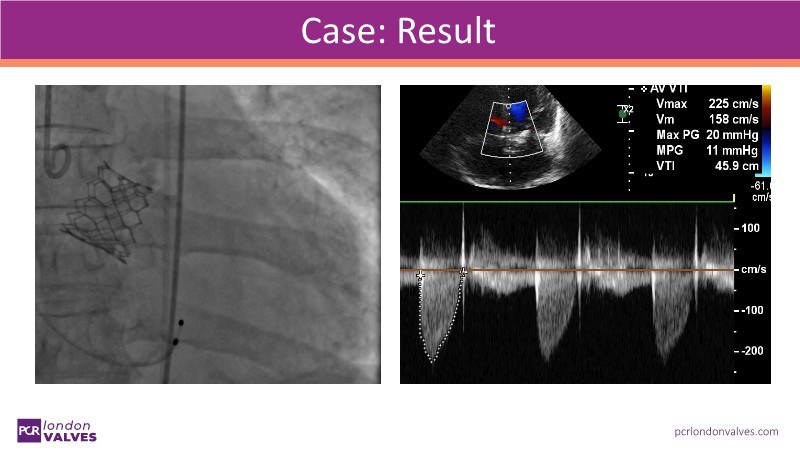

This session offers an in-depth review of complex TAVI cases, focusing on overcoming clinical challenges and achieving optimal outcomes with the Evolut FX+ device. Participants will learn about recent advances in TAVI indications for younger and asymptomatic patients, strategies for managing TAV in surgical aortic valve (SAV) patients including redo TAVI, and explore technological innovations designed to address complex anatomical scenarios.